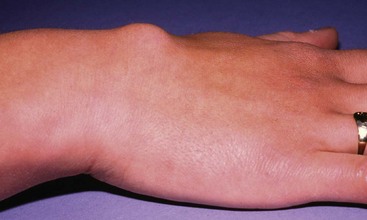

This extremely common and inappropriately named condition is a cyst-like lesion derived from the lining of a synovial joint, tendon sheath or embryological remnants of synovial tissue. The ‘cystic’ space does not usually communicate with the associated joint or tendon sheath, and like synovial joint cavities, is not lined by epithelium. It contains a colourless, gelatinous fluid. Ganglia present as superficial lumps, usually about 1–2 cm in diameter, though sometimes larger. They are most common on the dorsum of the forearm and hand (Fig. 46.15) and around the ankle. They are rarely painful but sometimes cause mechanical problems or interference with footwear. Ganglia are easily recognised by their smooth, hemispherical surface, and firm but slightly fluctuant ‘cyst-like’ consistency. The overlying skin is normal and mobile and the ganglion weakly transilluminable.